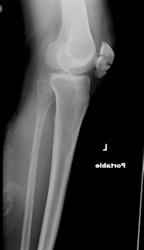

Patient 2: 38 y/o male experiencing knee pain after slipping on ice and hitting his knee on a rock

What 4 bones can you see in this x-ray image?

What type of injury likely occured in this patient?